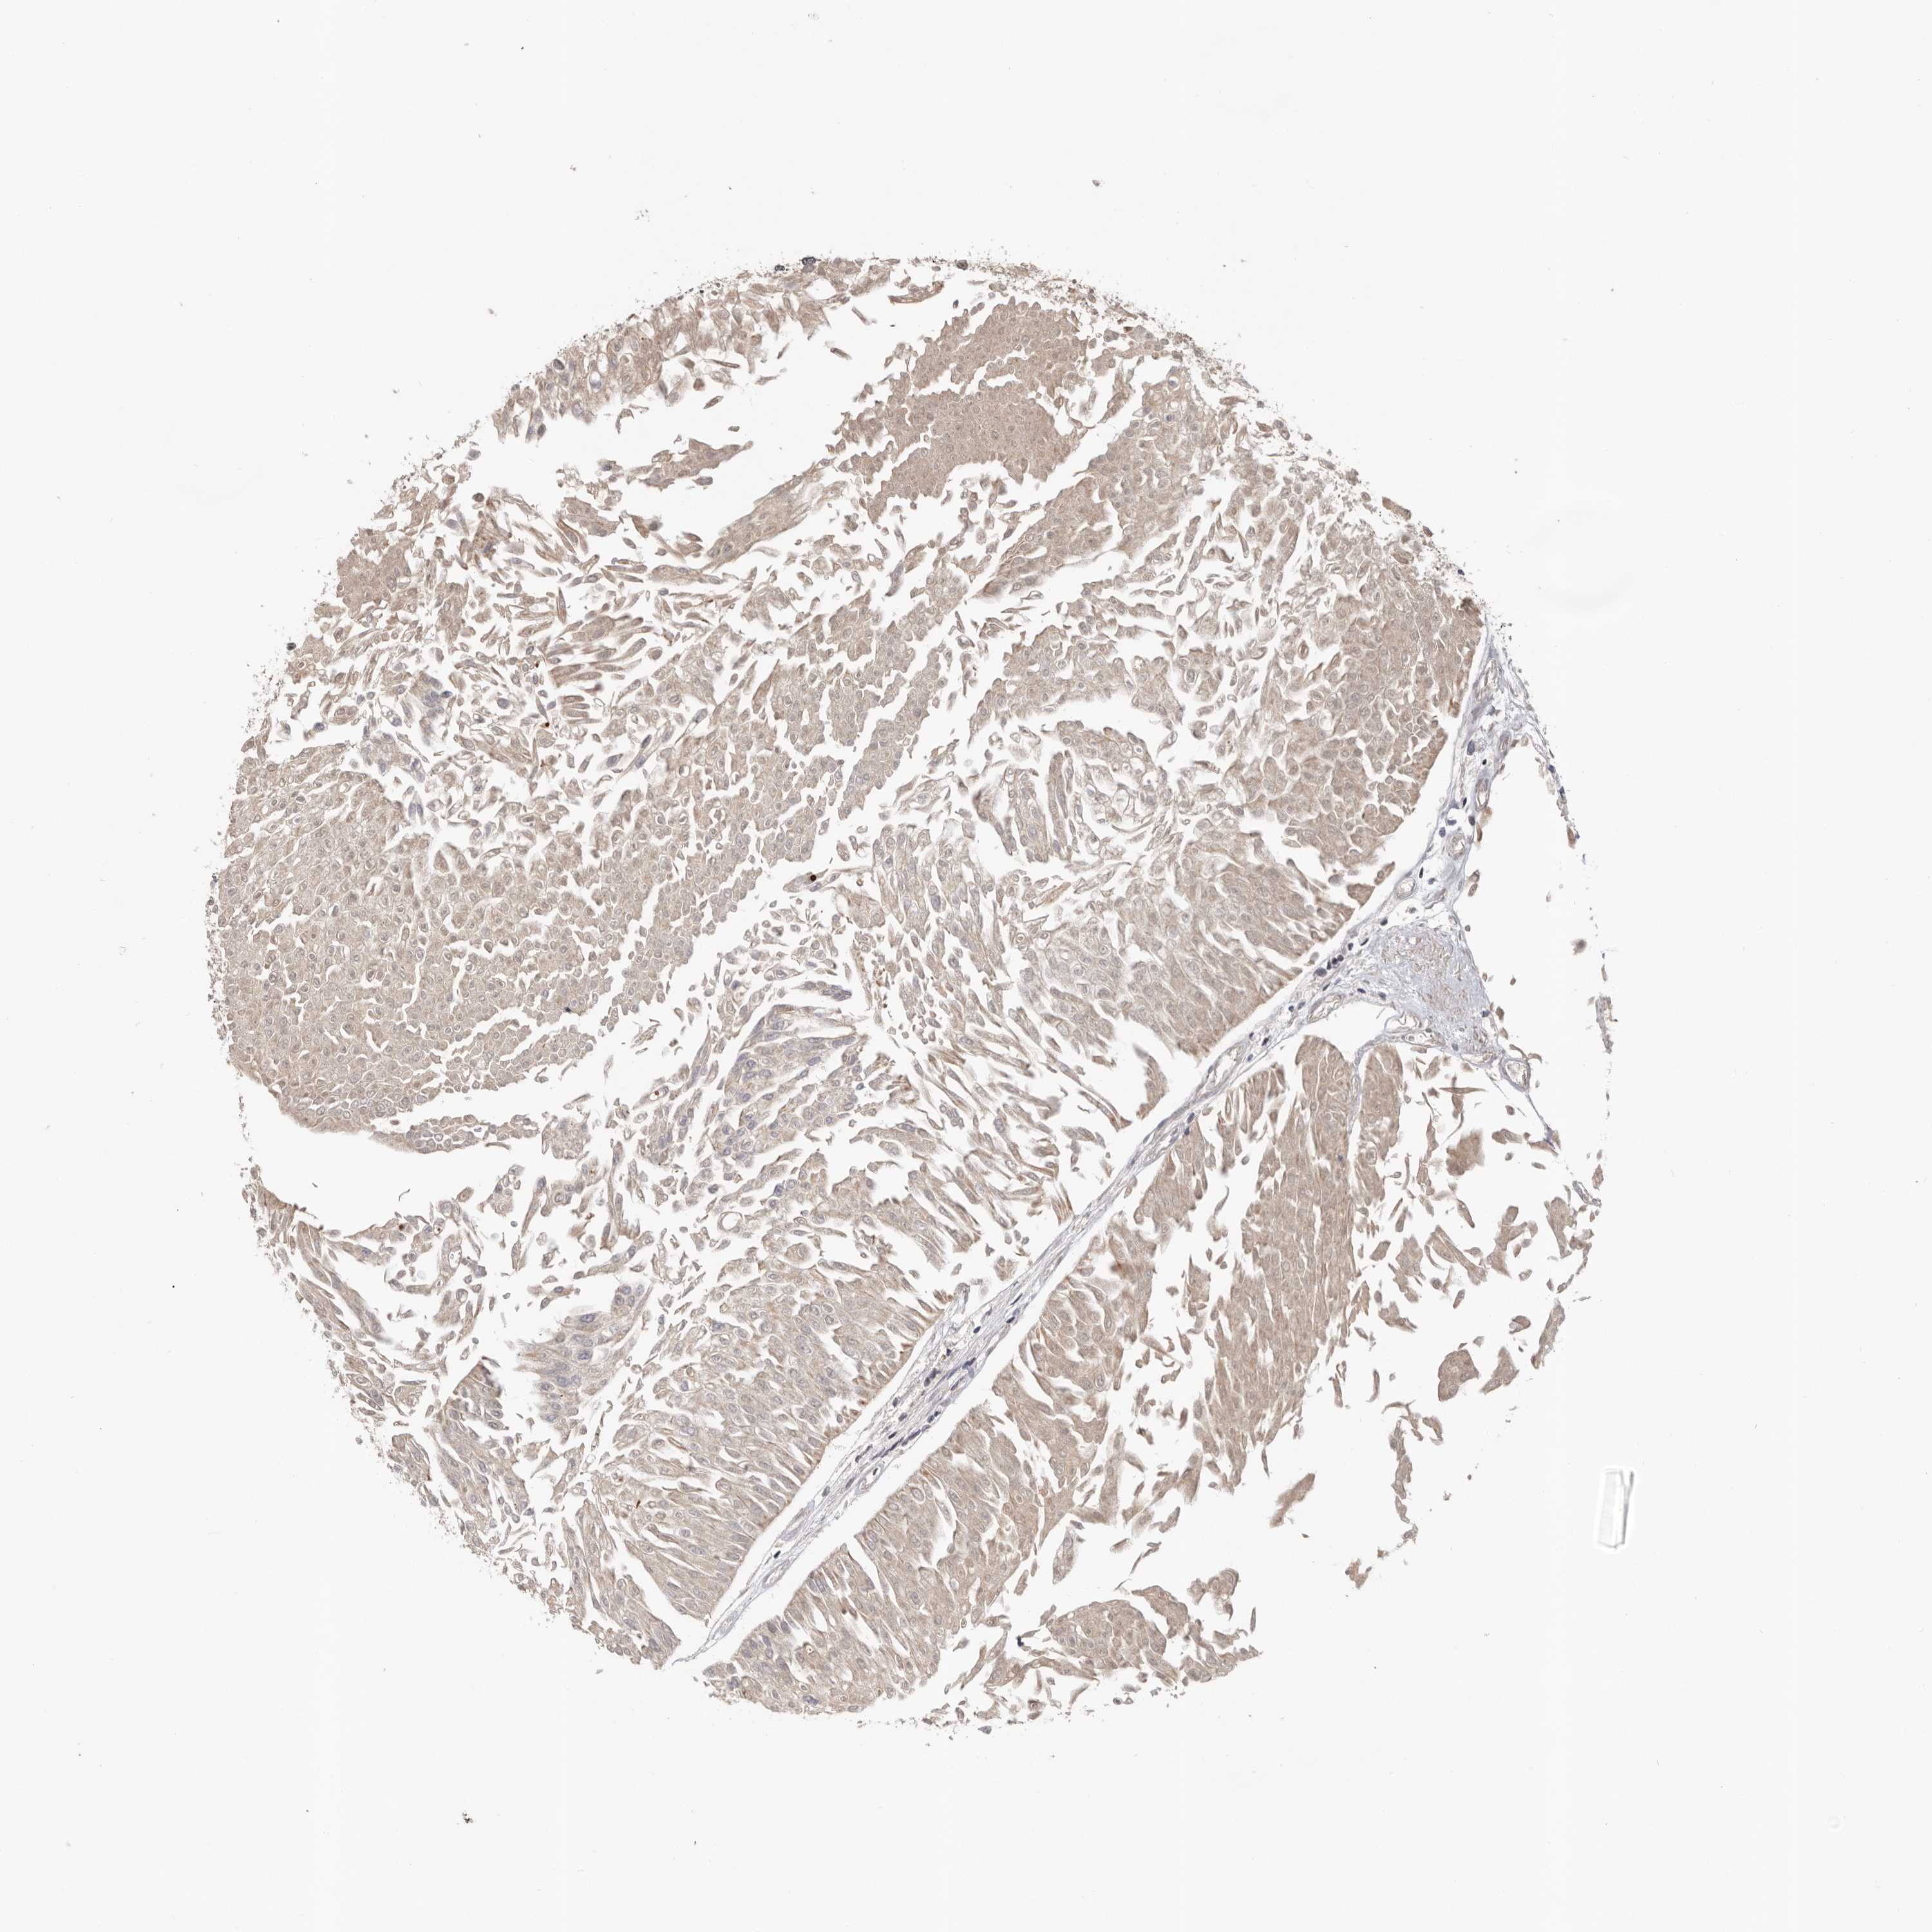

UROTHELIAL CANCER - Protein expressioni

A mouse-over function shows sample information and annotation data. Click on an image to view it in a full screen mode. Samples can be filtered based on level of antibody staining by selecting one or several of the following categories: high, medium, low and not detected. The assay and annotation is described here.

Note that samples used for immunohistochemistry by the Human Protein Atlas do not correspond to samples in the TCGA dataset.

Antibody stainingi

Antibody staining in the annotated cell types in the current human tissue is reported as not detected, low, medium, or high, based on conventional immunohistochemistry profiling in selected tissues. This score is based on the combination of the staining intensity and fraction of stained cells.

Each image is clickable and will lead to virtual microscopy that enables deeper exploration of all samples and also displays staining intensity scores, fraction scores and subcellular localization as well as patient and tissue information for each sample.

Antibody HPA024313

Antibody HPA027983

Antibody HPA028628

Urothelial carcinoma, Low grade

Urothelial carcinoma, High grade